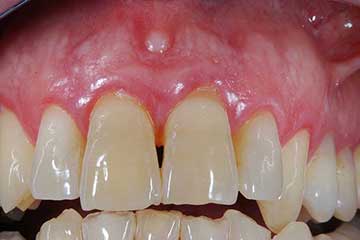

Lembo libero per correggere una recessione gengivale